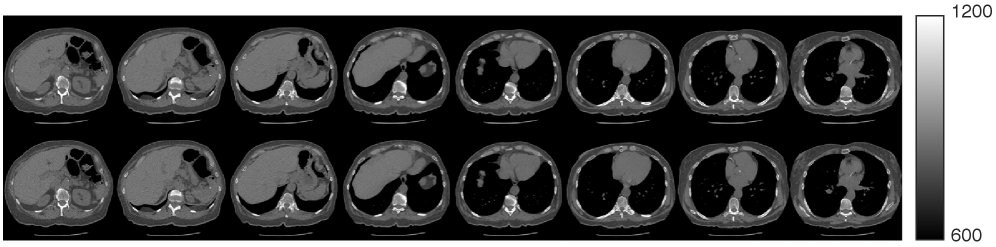

Our proposed method is able to learn a fully 3D prior on 256×256×256256\times 256\times 256 sized CT volumes, allowing it to generate high quality volumes. We used (7) with K=1K=1 and η=0.4\eta=0.4 and 200 steps for unconditional sampling. Figure 3 shows unconditional volume samples from LIDC-IDRI prior, visualized across axial, coronal, and sagittal slices. The top row shows slices from an unconditionally sampled volume, while the bottom row shows the nearest-neighbor volume from the training dataset. These results indicate that the proposed prior does not simply memorize from the training dataset and is capable of generating realistic high-resolution 3D CT volumes with fine-grained details of anatomic structure. Further generation results on different prior are in the appendix.

Refer to caption

Figure 3: Unconditional 3D image generation results using the LIDC-IDRI prior. The top row shows axial, coronal, and sagittal slices from a generated volume, and the bottom row shows the corresponding slices from its nearest-neighbor volume in the training dataset. The slice indices for the axial, coronal, and sagittal views are [30,80,130,180,230][30,80,130,180,230], [70,100,130,160,190][70,100,130,160,190], and [60,130,160,190,210][60,130,160,190,210], respectively